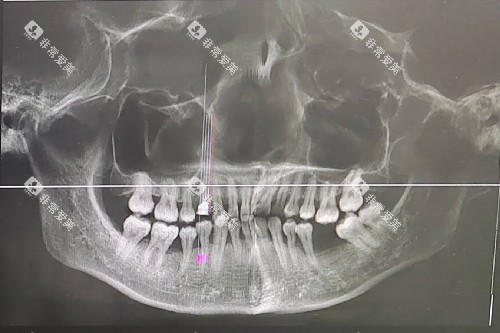

(二)口腔X光检查

口腔X光检查能够帮助医生更深入地了解牙齿的内部结构和牙槽骨的情况。

常见的口腔X光检查包括全景片和根尖片。

全景片可以清晰地显示全口牙齿的形态、位置以及牙槽骨的状况,收费大概在 80 - 150 元。

根尖片则主要用于检查单个牙齿的根尖周情况,价格通常在 20 - 50 元每颗牙。